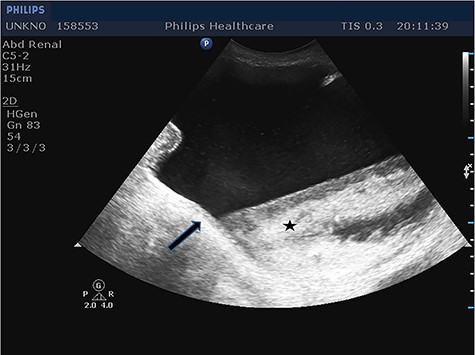

Given the fact that the patient was still hemodynamically stable, and in order to identify preoperatively the content of the incarcerated hernia sac, prompt imaging with ultrasound was considered necessary. Imaging revealed the protrusion of the entire bladder through the right internal inguinal ring and extending into the scrotum (Fig. 1), as well as hydronephrosis of the right kidney (Fig. 2), justifying the patient’s renal dysfunction.

Longitudinal ultrasound image of right kidney showed hydronephrosis. Same findings noticed in contralateral kidney (not shown).